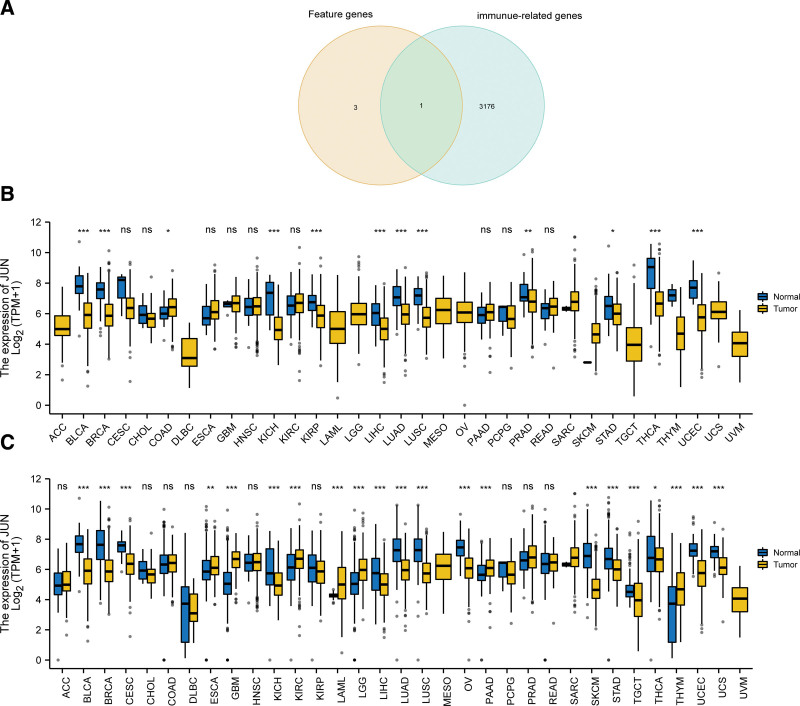

3.8. Immune-related key gene expression

We then identified the intersection of the feature genes we obtained and immune-related genes included in 2 prior knowledge database InnateDB (https://www.innatedb.com/) and Immport (https://www.immport.org/home). Ultimately, JUN was the only genes met the requirements (Fig. 10A). Taking impact of JUN in immunity to account, we envisaged that JUN may play a role in anti-tumor immunity and turned our sights to the expression of JUN in various cancer. In subsequent pan-cancer analysis in TCGA database, down-regulation of JUN in BLCA, BRCA, KICH, KIRP, LIHC, LUAD, LUSC, PRAD, STAD, THCA, UCEC and up-regulated expression in COAD were observed (Fig. 10B). Another pan-cancer analysis performed in TCGA and GTEx databases and resultantly indicated that JUN expressed at low levels in a variety of cancer types including BLCA, BRCA, CESC, KICH, LIHC, LUAD, LUSC, OV, SKCM, STAD, TGCT, THCA, UCEC, and UCS, whereas highly expressed in ESCA, GBM, KIRC, LAML, LGG, PAAD, and THYM (Fig. 10C).

To ascertain whether the obtained feature genes possess broader applicability, we combined our investigation with the current hotspot of immune infiltration. We extended these analyses to cancer, thereby enhancing the value of our research, and potentially broadening the applicability of these identified targets from OA to a more expansive context. By finding the intersection of immune genes obtained from InnateDB and Immport database and the 4 feature genes, we ultimately selected JUN to further explore its role in pan-cancer. We found that JUN were correlated with the clinical outcome (OS) of patients of BLCA, BRCA, CESC, CHOL, LGG, LUSC, and THYM. At the same time, we analyzed the TISIDB database and found a significant positively correlation between JUN expression level and lymphocytes, immunomodulators (including MHC molecule) and chemokines at pan-cancer level, especially in LGG. Therefore, above findings suggested that JUN had nonnegligible impact in shaping of the immune status in various cancers.